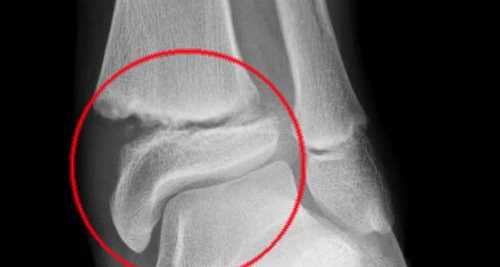

Ay, kemik kırıklarında kullanılacak bor katkılı malzeme üzerinden yapılan ön denemelerinden çok olumlu sonuçlar ortaya çıkartıldığına işaret ederek, söz konusu kemik implantların kullanımının ardından, kırıklarda olumlu sonuçlar belirlendiğini kaydetti.

"Normalde kemiklerin iyileşmesi çok uzun zaman alıyor ve pek çok enfeksiyon meydana gelebiliyor. Bu çalışma ile söz konusu enfeksiyonların ürettiğimiz malzeme kullanıldığında hiç oluşmadığı ve enfeksiyonu önlemek için kullanılan ilaçlara gerek kalmayacağı saptandı. Bu yeni geliştirilen malzeme ile kemik iyileşmesi normal süresinin yarısı kadar bir zamanda gerçekleşiyor. Sonuçta enfeksiyon riski yok, kemik oluşumu çok hızlı ve beklenen süresinin yarısı kadar süreçte kemik iyileşmesi meydana geliyor. Bu buluş, kemik kırık problemi yaşayan kişilerin yaşam kalitesinin yükseltilmesine katkı yapacaktır."